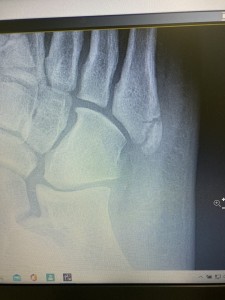

↓怪我して13日目のレントゲン写真(10/17)

画像荒くてよくわからないと思いますが、

骨折したところがよくわかり、白いモヤが写ってるんですが、仮骨(かこつ)という新しい骨ができているということです。

経過としては良好です✨